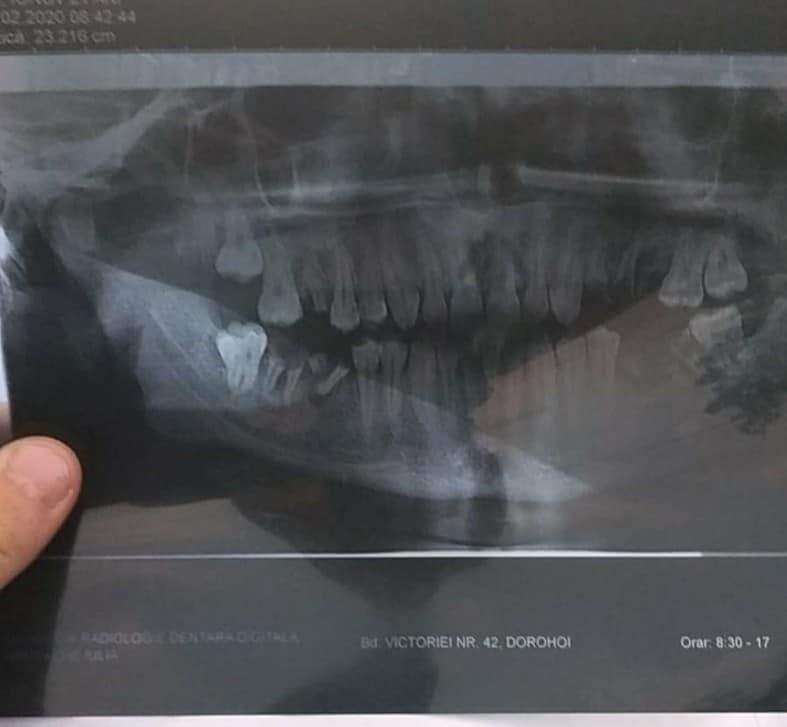

„E foarte grea și dureroasa boala pe care o duce pe umeri Mihai, iar că o veste și mai grea mi-a zis că are în gura aproape toata dantura stricata și trebuie să facă în jur de 15 extracție și apoi pusă o lucrare dentară. Nu stia daca are voie să cheltuie bani și sa-si poată repara dantura…A zis ca el ii strângea pentru o casuta a lui daca operatia nu se mai poate efectua nefiind recuperabilă. Cu banii pentru intervenții chirurgicale,Mihai își va repara dantura și va merge în continuare la medici pentru fizioterapie, iar casuta rămâne un vis pentru el…Dacă se oferă cineva din cabinetele stomatologice să-l ajute pe Mihai sa-si repare dantura va rog dati-ne de stire. Tel: 0757139794 Simona Elena. Noi am luptat sa-l ajutam pe Mihai sa poata merge normal și să numai aibe dureri. Din pacate nu întotdeauna totul se termina cu bine, si din pacate aceste intervenții chirurgicale nu se pot face deoarece sunt prea multe riscuri.La aflarea acestor veștii Mihai a fost internat de urgență la psihatrie cu diagnosticul de tulburare anxioasa, dar acum mulțumită medicilor și bunului D-zeu starea lui de sănătate este buna”; spune Simona Elena Suhan.